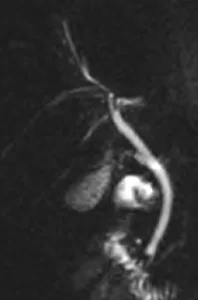

Figure 3. Chez ce patient non coopérant, mêmes les coupes de bili-IRM 2D sont trop artefactées pour permettre une analyse fiable des voies biliaires (A).

Cependant, de simples coupes axiales T2 (en mode d’acquisition très rapide) montrent le bas cholédoque dilaté sur la coupe (B), et son obstruction par un calcul sur la coupe sous-jacente (C)